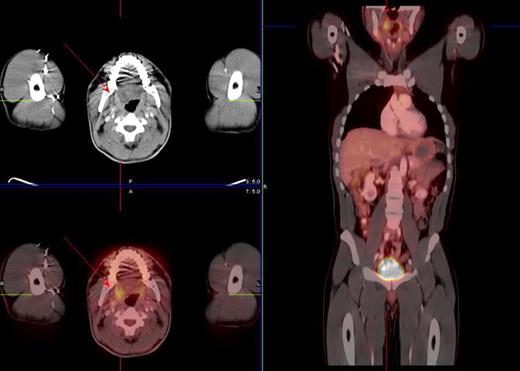

Restaging PET scan showing increased FDG tonsil uptake (red arrows) in a 38-year-old male patient with Hodgkin's disease stage II status post ABVD chemotherapy. Tonsillectomy was negative for malignancy.